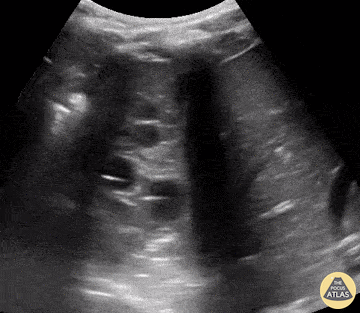

Pediatrics - Hepatization of the Lung

A 15-month-old male presented with cough, fever, and tachypnea of 3-days duration. POCUS revealed findings of right lung consolidation, consistent with pneumonia referred to as hepatization of the lung. Seen here territories above and below the diaphragm show ultrasonographic findings resembling liver parenchyma. Amar Singh, MD. Pediatrics specialist in Louisville, KY